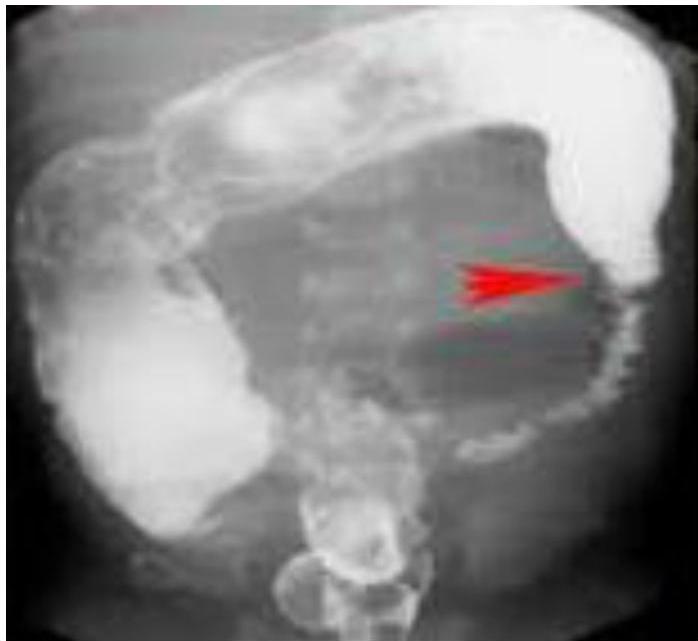

Intussusception

- 18 Months old boy presented with crying and vomiting.

- A bloody stool was passed on the day of the imaging examinations (classically described as “currant jelly” stool).

Diagnosis? Ileocolic intussusception.

Investigation? Barium enema.

Sign?

- Cut-off sign in the middle

- Coiled spring appearance / spring sign / target sign

Etiology:

- Idiopathic

- Secondary to: HSP, intestinal polyps

Emergency:

- Type of obstruction

Treatment:

- NPO/IV fluids

- NGT aspiration

- IV antibiotics

- Hydrostatic reduction with Barium/air enema

- Laparotomy and resection if needed

Complications:

- Ischemia and necrosis